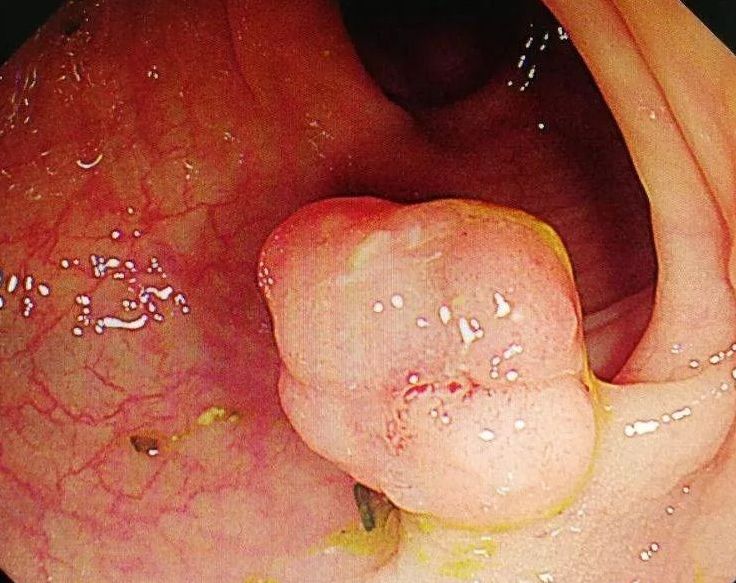

接着就是接二连三的切结肠息肉,一种即将或终将癌变的病变~如果生命够长。

息肉,尤其是腺瘤性息肉,是潜伏的杀手,如果有足够的时间,总有一天会癌变。

各种各样的息肉,大的小的,扁平的,无蒂的,亚蒂的,粗长蒂的,不同部位的层出不穷。

我们将其一一切除。